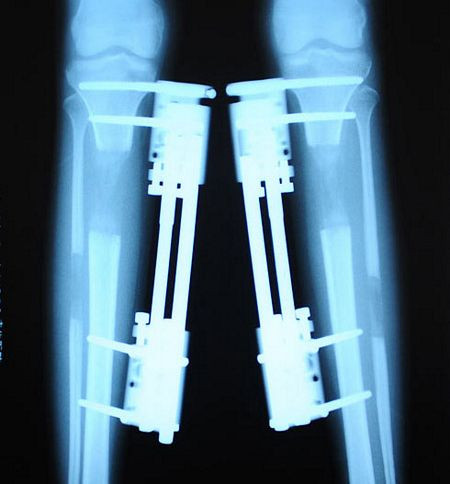

Hình ảnh chụp X-quang của một cô gái kéo dài xương chân.

Nguyên lý của phương pháp kéo dài xương chân là cắt rời một chỗ trên đoạn xương chân cần kéo dài, xuyên các đinh chuyên dụng qua cả hai đoạn xương rời ra, rồi gắn vào một loại khung cố định đặc biệt ở bên ngoài chân.

Đợi đến khi xương mới liền, người ta lại chỉnh vít trên khung bên ngoài, cho giãn ra khoảng 1mm/ngày ( kéo dài 2mm/ngày thì xương không kịp phát triển hoặc phát triển sẽ gây vẹo, méo, nếu chỉ kéo 0,5mm sẽ gây liền dính) nhằm mục đích bắt buộc các tổ chức xương phải tiếp tục lan ra để nối liền với nhau. Và cứ như vậy.... cho tới khi đạt được chiều dài xương chân như dự tính.

Được biết, khi tiến hành thẩm mỹ kéo dài chân, mỗi ngày cô gái đều phải tiến hành chỉnh đinh vít 3 lần, mỗi lần đinh vít sẽ được đưa sâu vào trong khoảng 7mm.

Sau nhiều tháng, đôi chân của cô gái sẽ dài ra. Tuy nhiên, mức độ đau đớn cũng như những biến chứng sau phẫu thuật sẽ đeo đuổi cô gái này suốt cả cuộc đời.

Sau khi cố định xương, cô gái phải nằm bất động 35 - 40 ngày. Đến khi tháo khung, chân vẫn luôn ở trong tình trạng rỉ máu.

Trung bình để kéo dài xương chân 5-7cm, bệnh nhân phải mang khung cố định 10-12 tháng, sau khi bỏ khung, bệnh nhân lao động, sinh hoạt hoàn toàn bình thường, các phần xương chân được kéo dài thêm có độ cứng chắc như xương cũ.